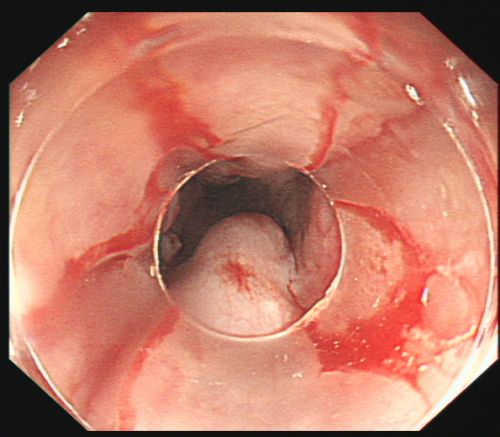

治疗后,创面无活动性出血。

由于血管压力高,手术风险大,术中发生大出血、窒息及异位栓塞的风险非常高。综合内科主任彭娅反复与家属沟通取得理解配合后,为易某实施改良后内镜下止血技术——食管曲张静脉套扎+硬化剂注射治疗。所幸手术过程顺利,术后继续予以降门脉压力、护胃、减轻腹水、维持内环境稳定等对症支持治疗。经过积极治疗,患者病情趋于稳定,已恢复饮食,精神状况好转,于215日出院。